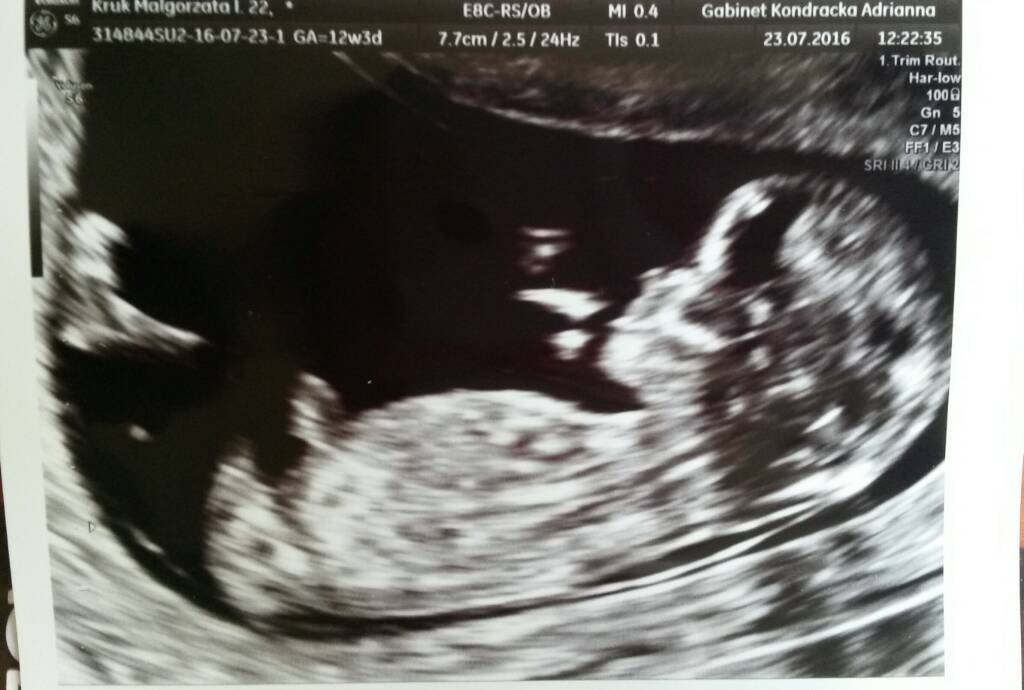

Moje słoneczko ma 6cm :) wszystkie pomiary bardzo dobrze wręcz idealne :) z tego usg wychodzi 12t3d czyli 2 dni do przodu i termin wyrównał mi się z terminu z om na 1.02 :) stopka ma już 1cm :) płci Pani doktor nie chciała mówić, bo mówiła że teraz może być równie dobrze przerosnieta lechtaczka lub już penisek ;) i jeśli bardzo będzie nas korcić to możemy sprawdzić w 16 tygodniu,także nadal każde może upierac się przy swoim ja mam synia, Kamil corcie ;) Doktor przemiła, wszystko nam tłumaczyła, o dziecku mówiła już jak o małym czlowieczku, a nie plodzie, super się u niej czuliśmy i na kolejne ważne usg na pewno będziemy chodzić do niej :) Każdej z Was dziewczyny życzę takiej wizyty u takiego lekarza <3

Moje słoneczko ma 6cm :) wszystkie pomiary bardzo dobrze wręcz idealne :) z tego usg wychodzi 12t3d czyli 2 dni do przodu i termin wyrównał mi się z terminu z om na 1.02 :) stopka ma już 1cm :) płci Pani doktor nie chciała mówić, bo mówiła że teraz może być równie dobrze przerosnieta lechtaczka lub już penisek ;) i jeśli bardzo będzie nas korcić to możemy sprawdzić w 16 tygodniu,także nadal każde może upierac się przy swoim ja mam synia, Kamil corcie ;) Doktor przemiła, wszystko nam tłumaczyła, o dziecku mówiła już jak o małym czlowieczku, a nie plodzie, super się u niej czuliśmy i na kolejne ważne usg na pewno będziemy chodzić do niej :) Każdej z Was dziewczyny życzę takiej wizyty u takiego lekarza <3 Zobacz załącznik 764018